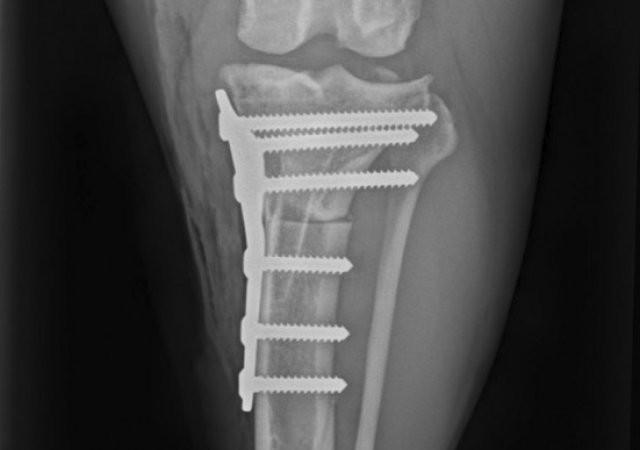

Zur Stabilisierung betroffener Knie empfehlen wir, unabhängig von der Größe des Patienten, die TPLO (Tibia Plateau Leveling Osteotomie).

Frakturbehandlung:

• Plattenosteosynthese

• TPLO